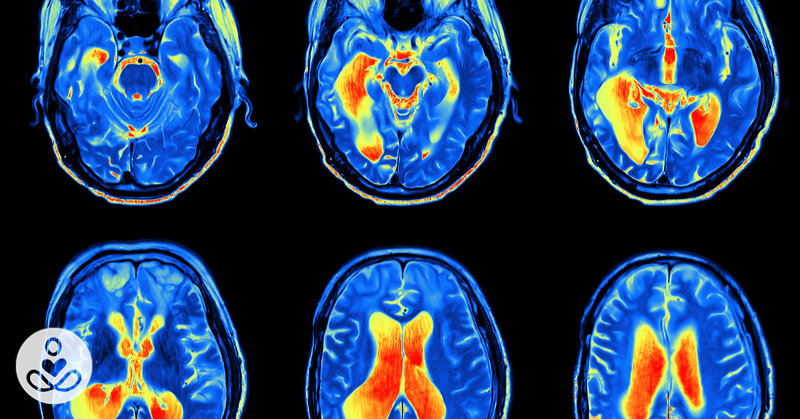

How complaining physically rewires your brain to be anxious and depressed : The Hearty Soul

I’m pretty sure we can all pick out that one person who is a consistent negative ninny. The one person who we think sees the glass half empty, but who insists that they are just a hard-edged realist. For me, it is one of my long time childhood friends Sam. Things are never good enough… View Article